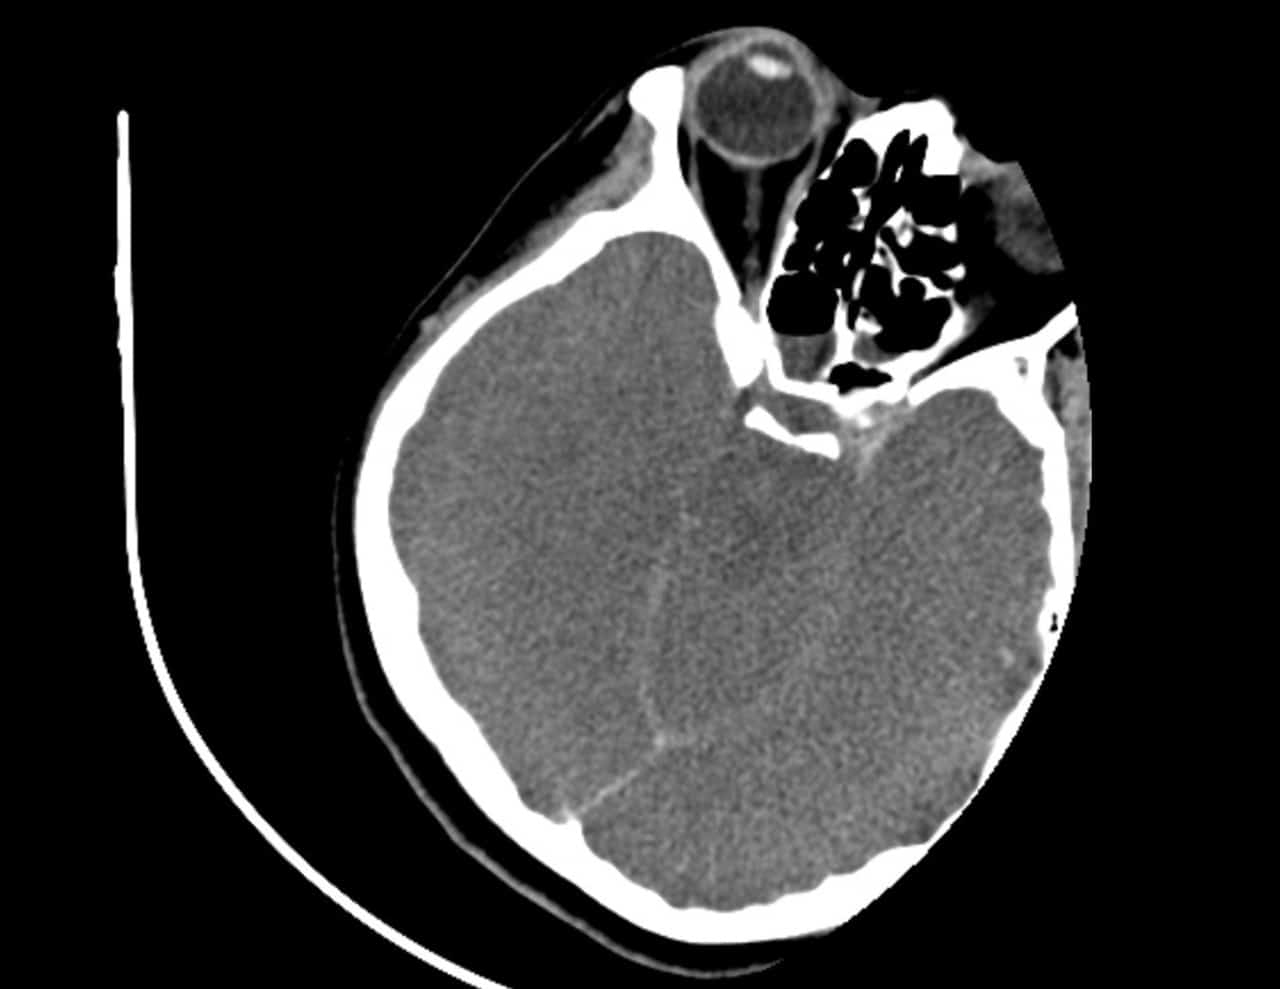

Nữ bệnh nhân ngộ độc lá ngón, tổn thương não. (Ảnh: bachmai.gov.vn)

Phim chụp cho thấy não của bệnh nhân T. bị tổn thương, phù nề (Ảnh: bachmai.gov.vn)